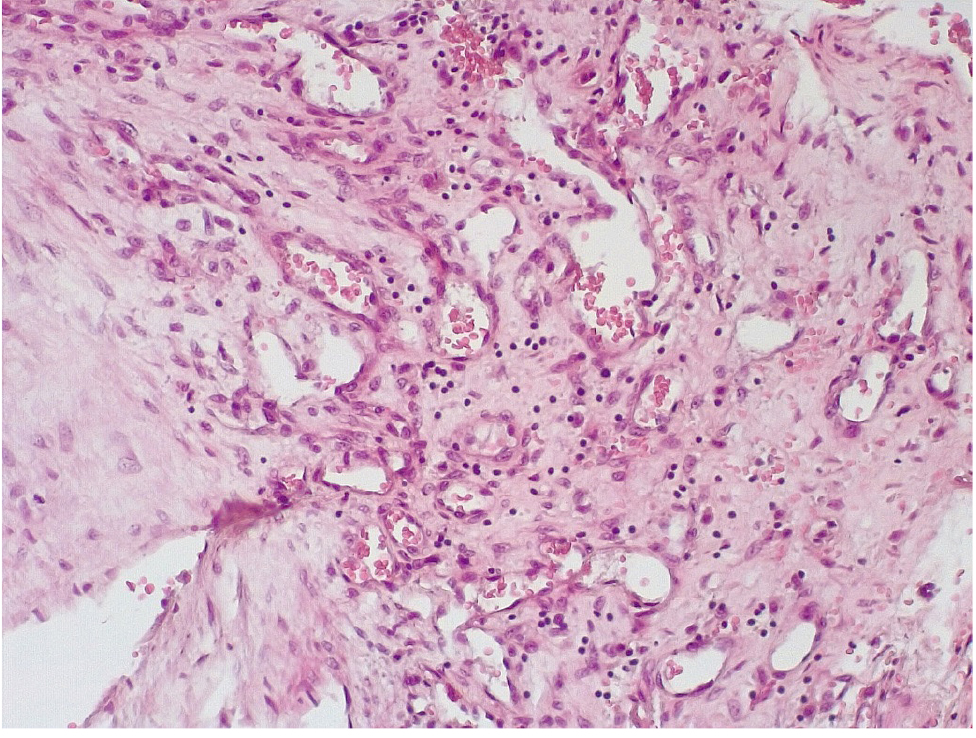

Патоморфологическое исследование стенок КА в ранние сроки после стентирования выявило характерные особенности. В течение первых 3 дней после стентирования в стенке КА имелась атерома с признаками геморрагий. Эндотелий был на большем протяжении разрушен, с признаками десквамации, с окружающей очаговой лейкоцитарной инфильтрацией. Вокруг атеромы, со стороны медии и адвентициальной оболочки, отмечалась умеренновыраженная лимфоцитарная инфильтрация (рис. 1).

Обращало внимание, что в местах «оголенного» эндотелия КА отмечалась слабая экспрессия белка CD31, что указывало на выраженные дистрофические и некробиотические изменения клеток (рис. 2). При этом экспрессия ФВ была яркой, выраженной на всем протяжении интимы КА (рис. 3).